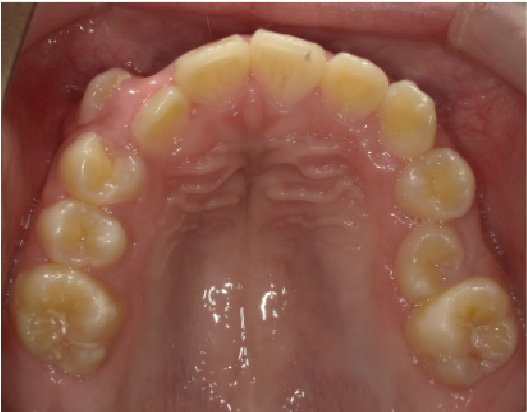

狭い歯列(狭窄歯列)によって、舌が歯列の中に収まらない状態です。

●高口蓋 ●低位舌 ●口呼吸

狭窄歯列(高口蓋)

右のように、狭窄歯列だと舌は、狭い歯列に阻まれて、前方や上方の口蓋に自由に動くことができません。その結果、舌は低い位置(低位舌)にあり、前方に出ず後方に位置するので、気道が狭くなってしまっています。

一方、左のように、広い歯列だと舌は、前方にも上方にも自由に動けるので、舌は普段は口蓋についていて鼻呼吸が無理なくできているのです。

狭い歯列(狭窄歯列(きょうさくしれつ))

高口蓋(上顎が深い→鼻腔が狭い)

舌が歯列に納まらない→低位舌